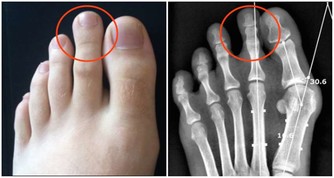

因為,這會把耳垢推入耳朵深處,造成聽力下降,甚至損壞耳膜。

耳垢一般只會出現在外耳道。

但因為人們總是用棉花棒清理,將耳垢推向耳朵深處,造成阻塞。